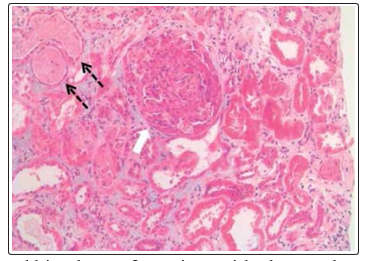

Fig. 1 shows the renal histology in a patient with class IV LN.

Figure 1: Renal histology of a patient with class IV lupus nephritis (white arrow shows a glomerulus with cellular crescent; black broken arrows show adjacent tubules with red cell casts)